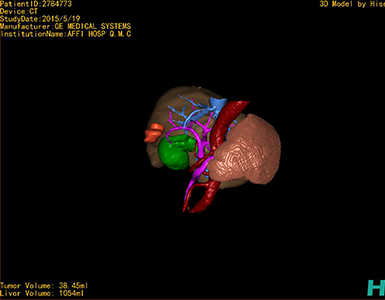

通过调节窗宽窗位调整CT序号,对肿瘤,肝实质,胆囊,下腔静脉,肿瘤,肝动脉、门静脉及肝静脉等进行三维重建;系统自动计算肿瘤体积和肝脏体积。

模拟手术操作,自动计算切除肿瘤体积。肝脏体积为1054ml,肿瘤体积为38.45ml,肿瘤体积为肝脏体积的3.6%,通过比对50-60岁正常肝脏体积为1330.41±329.13 ml,通过术前模拟手术,精准判断切除后剩余肝脏体积能耐受,避免肝衰竭发生。

术前三维重建:

重建图片